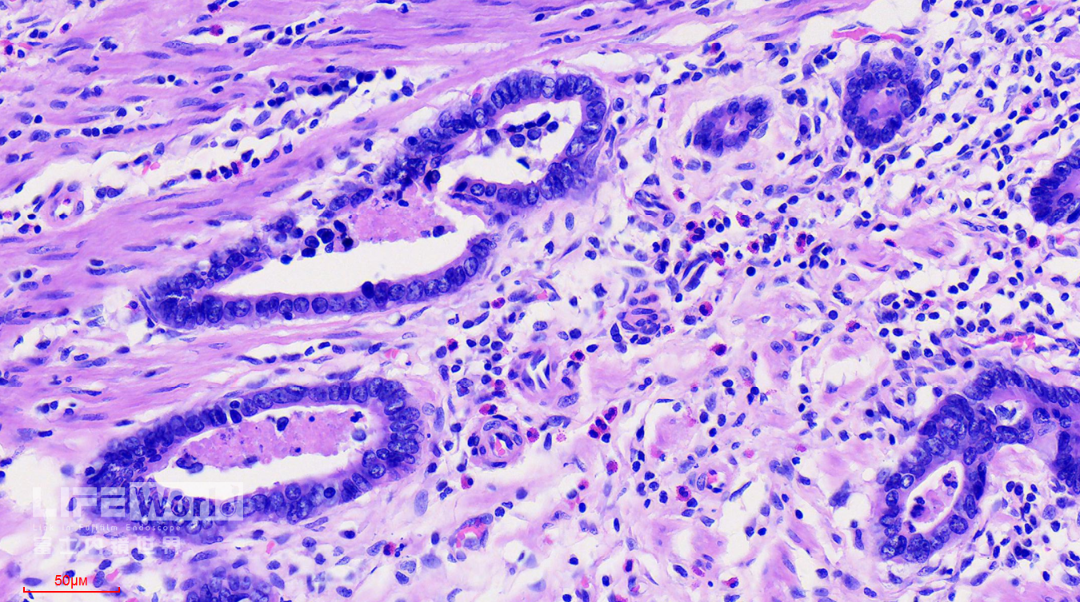

HE染色:2号切片示中分化腺癌,6号切片示高级别上皮内瘤变,局灶癌变。

病变处(红圈内)可见不规则的腺管状结构,部分呈筛网状。图中可以看出,病灶间可见相对正常的胃底腺结构。图片中最深的病灶已经侵及粘膜肌层。

病变处细胞异型性明显。病变内部可见多处扩张的腺管,内部可见坏死碎片。对应胃镜图片上的白色球状物。